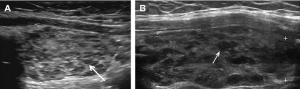

fig-5-micronodular-pattern-in-hashimotos-thyroiditis-a-sagittal-image-of-the

Thyroid Ultrasound